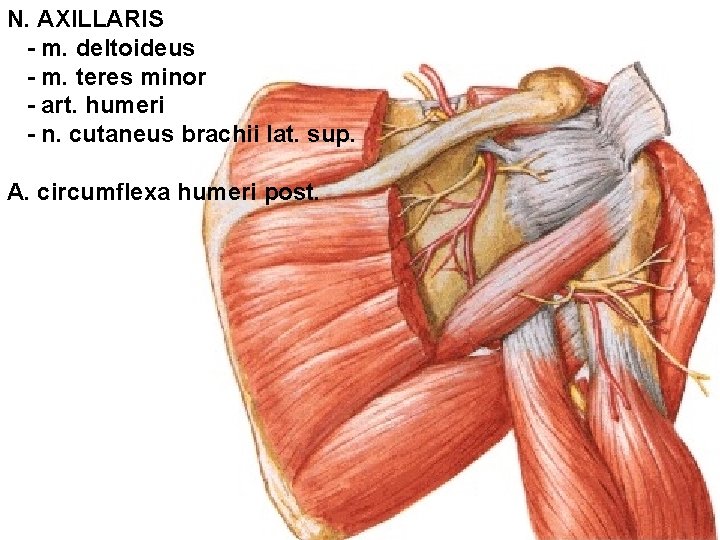

N. AXILLARIS (foramen humerotricipitale)

N. AXILLARIS - m. deltoideus - m. teres minor - art. humeri - n. cutaneus brachii lat. sup. A. circumflexa humeri post.

N. cutaneus brachii lat. sup.